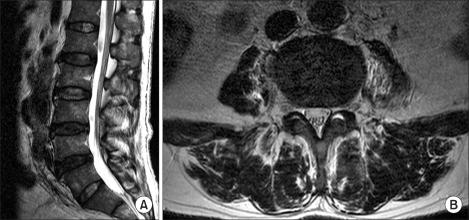

脊柱沙门氏菌感染是一种罕见疾病,通常发生于已有镰状细胞贫血的患者,而在无镰状细胞贫血的患者中更为罕见。一名 61 岁男性患者因肾功能评估而住院,随后开始治疗其背痛。他的背痛大约在 2 个月前无明显诱因出现,最初的腰椎 MRI 仅显示椎间盘膨出。关于他的发热,诊断为可能为非典型性肺炎、丛林斑疹伤寒等,给予了多种抗生素治疗。转科时,白细胞和 hs-CRP 正常,ESR 升高。为他的背痛进行了诊断性硬膜外阻滞,但症状未改善。再次进行腰椎 MRI 检查,结果显示感染性脊柱炎的发现。脓肿培养出沙门氏菌 D,因此诊断为脊柱沙门氏菌感染。经抗生素治疗后,他的背痛改善,能够行走。